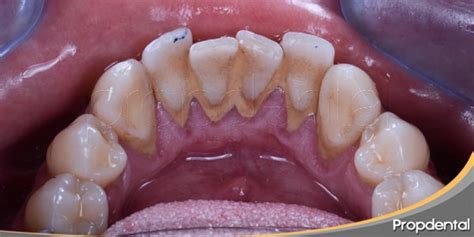

El sarro dental, también conocido como cálculo, es un depósito duro de color amarillento o marrón que se forma en los dientes. Está formado por partículas de comida, bacterias y otros microbios que se quedan atascados en nuestra boca y acaban calcificándose (endureciéndose). El sarro es una superficie pegajosa y áspera que permite que las bacterias se adhieran con facilidad.

El sarro se presenta en dos formas: el sarro supragingival, que se forma por encima de la línea de las encías, y el sarro subgingival, que reside por debajo de la línea de las encías.

Lo primero es lo primero: mírate en el espejo. Si ves manchas descoloridas en tus dientes delanteros que no parecen desaparecer con el cepillado, puede ser un signo de sarro dental. El sarro dental tiene el aspecto de manchas amarillentas o vetas de color marrón oscuro a lo largo de la línea de las encías o en cualquier zona donde se acumulen partículas de comida.

Otra forma de saber si tienes sarro dental es palpar alrededor de los dientes con la lengua. El sarro dental se sentirá áspero y abrasivo, a diferencia de una superficie lisa cuando no tienes sarro.